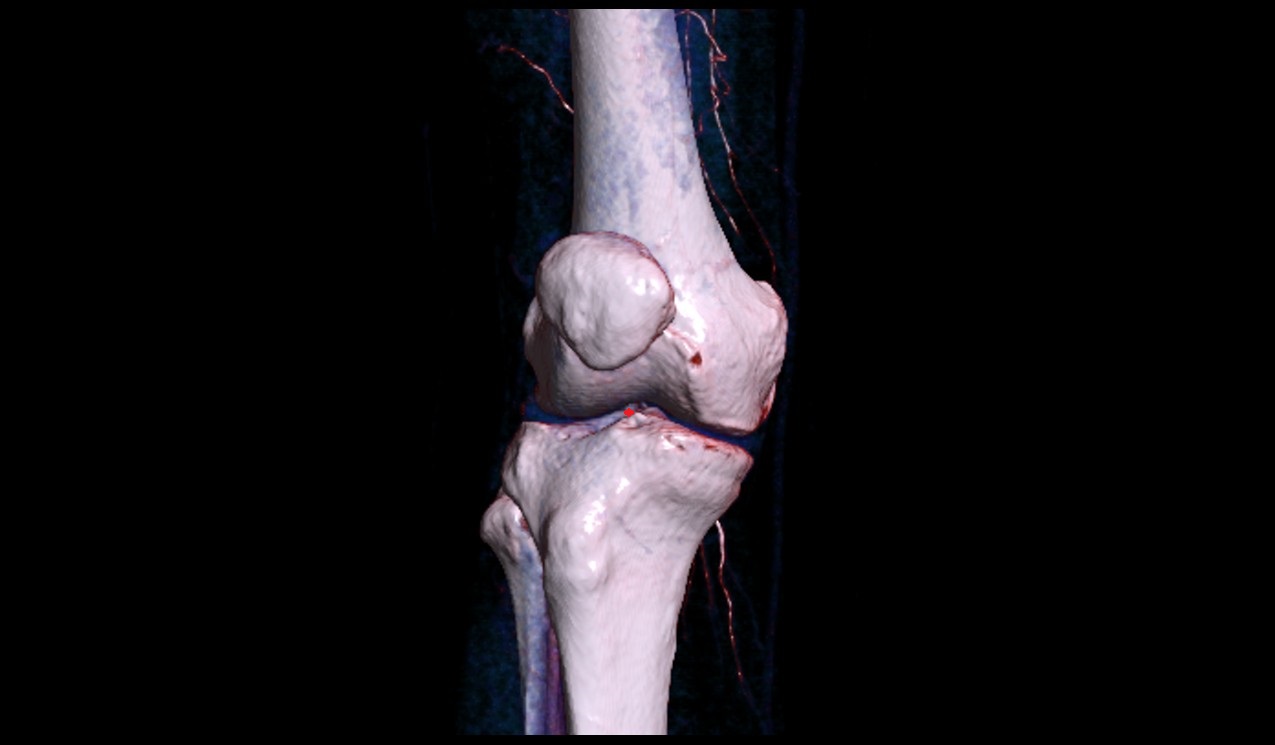

- Knee Joint